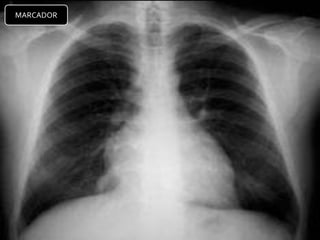

MARCADOR

CRITERIOS DE EVALUACIONRX. TX.  Pulmones desde ápex hasta senos costo diafragmáticos  Pulmones y corazón sin rotación.  10 pares de costillas.  Sombra área de la tráquea centrada sobre la columna.  Balance en los contrastes de la imagen (exposición adecuada).

INTERPRETACION  Revisar estructuras óseas.  Partes blandas.  Espacios intercostales.  Parénquima pulmonar  Nivel de los senos costodiafragmaticos.  Neumatización.  Trama alveolo-pulmonar  Silueta cardiaca  Cayado aórtico.